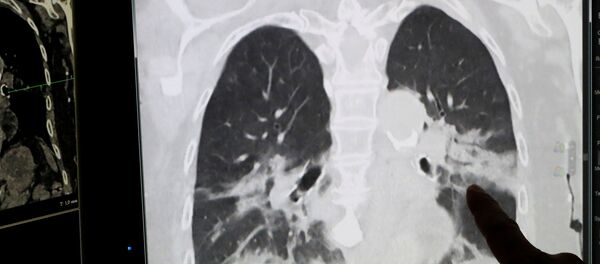

据专家数据,美国有症状新冠肺炎感染者的死亡率为1.3%,而季节性流感的死亡率仅维持在0.1%。专家是基于33个州116个县的新冠肺炎确诊及死亡病例数据进行的统计。

据专家预测,如果美国和其他国家不开始更加积极地对抗疫情,那么死亡人数可能会是灾难性的。

世界卫生组织3月11日宣布新冠肺炎为大流行病。该组织最新数据显示,全球新冠肺炎确诊病例累计超过460万例,死亡超31.1万例。

美国累计确诊超150万例,死亡逾9万例。